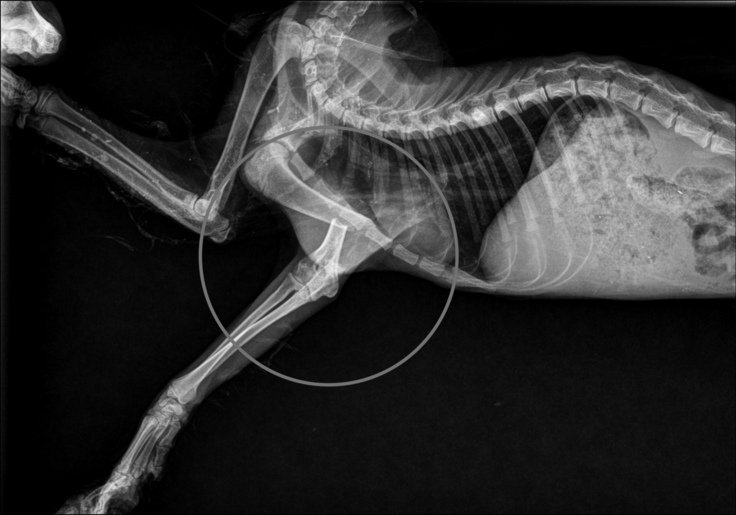

1週間〜2週間に1度レントゲンで状態を確認しています。 外からピンを固定する方法を希望していましたが、手術をしてくださった先生のその場の判断で外と中どちらからも固定をする手術となりました。

経過観察後、外側のピンを抜く手術は無事成功し、内側のピンはひとまずそのままにしておくことになりました。特に異常がなければ生涯このままでも問題ないとのことですが、拒否反応が起きると手術をしてピンを抜かなければならないとのことです。

▼創外固定抜去手術後の経過写真